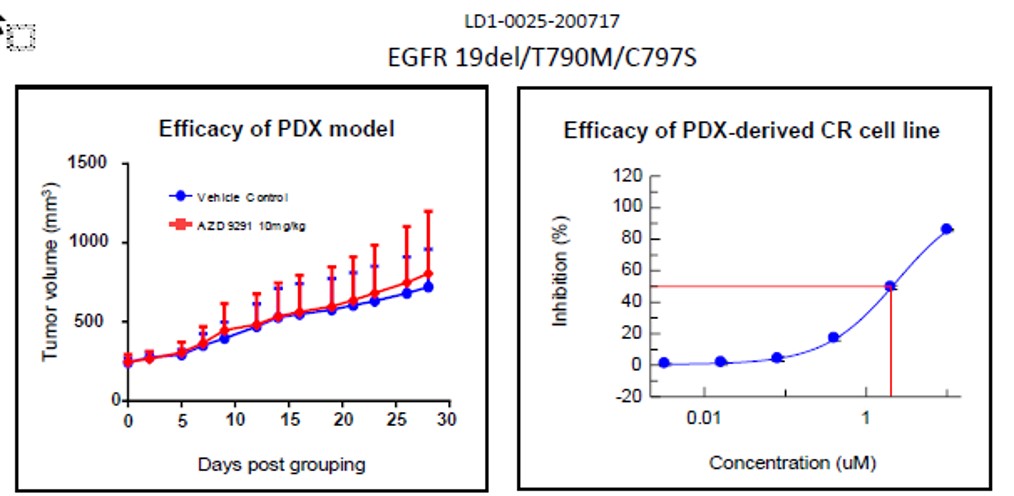

LIDE validated this separately to ensure established CR cells demonstrate heterogeneity like its parental PDX tumors. Below is an example of EFGF mutant PDX models and CR cell lines, showing model drug sensitivities are similar.

Fig. Efficacy results of LD1-0025-200717. IC50 of CR cell line was 2.01, indicating drug

insensitivity, as expected and matching result of PDX model